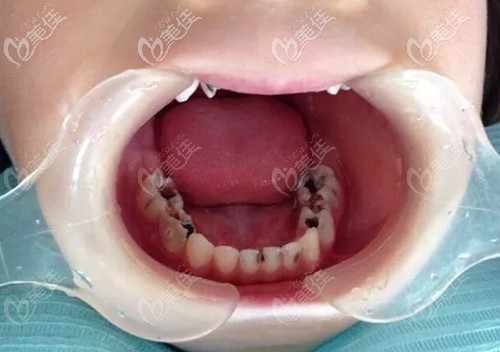

五六歲兒童乳牙齲齒需要盡快治療嗎?這些利弊你一定要知道!

五六歲兒童乳牙齲齒需要盡快治療嗎?當然了,因為不及時治療乳牙齲壞很容易壞到牙髓腔,影響恒牙萌出,導致牙齒擁擠不起,這些弊端大家一定要明白!